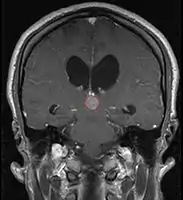

Pineal Gland Tumors

Clinical Presentation

- Determined by the spatial anatomy and direction of growth

- Obstruction of aquaduct: hydrocephalus presenting as headaches, nausea, vomiting

- Compromise of superior colliculus: vertical gaze palsy, pupillary and oculomotor nerve paresis (Parinaud syndrome)

- Progressive growth: cranial nerve neuropathies, hypothalamic dysfunction

- Work-up includes MRI, CSF, serum markers for bHCG and AFP